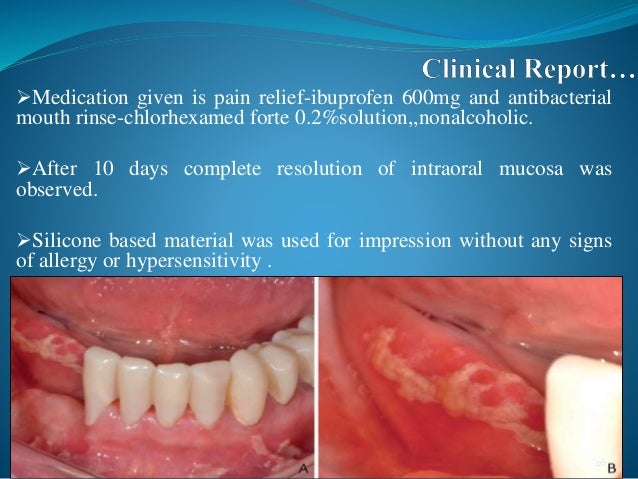

Clinical Characteristics Of An Allergic Reaction To A Polyether Denta…

www.slideshare.net

www.slideshare.net

allergic reaction impression polyether clinical

Clinical Characteristics Of An Allergic Reaction To A Polyether Dental

www.thejpd.org

www.thejpd.org

impression polyether allergic reaction mucosa preoperative